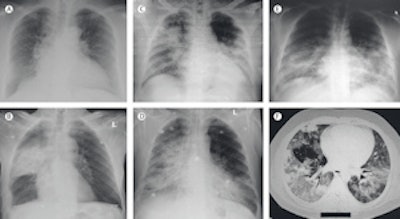

Imaging findings at presentation in Saudi patients with MERS. All images courtesy of Lancet Infectious Diseases.

Because the x-ray and CT features of MERS-CoV are not different from any case of pneumonia, the best thing radiologists can do is to alert the physicians and have a high degree of awareness of the possibility of MERS-CoV infection in any case of pneumonia, according to co-author Ali Zumla, PhD, a professor of infectious diseases and international health at University College London. A detailed history of travel to the Arabian Peninsula may point toward the possibility of MERS-CoV infection, he added.

"Like any other chest infection, there is no imaging modality that can help make a specific diagnosis. Any changes in the imaging should be followed up by a request for a MERS-CoV-specific diagnostic test, including tests to rule out bacterial and other viral causes of pneumonia," he told AuntMinnieEurope.com.